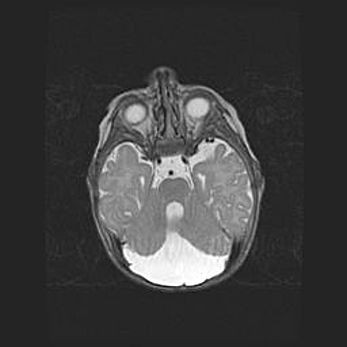

Мальформация Денди-Уокера. Киста задней черепной ямки.

Агенезия мозолистого тела.

Возраст: 2,5 месяца

Вес: 2420 г

Пол: женский

Окружность головы: 37 см

Срок гестации: 32 недели

Мальформация Денди—Уокера — редкий вид патологии ЦНС, представляющий собой врожденный порок развития каудального отдела ствола и червя мозжечка, ведущий к неполному раскрытию срединной (Мажанди) и латеральных (Лушка) апертур IV желудочка мозга. Для этогно синдрома характерна триада симптомов: гипотрофия червя мозжечка и/или полушарий мозжечка, кисты задней черепной ямки, гидроцефалия различной степени. В 70% случаев порок сочетается и с другими аномалиями головного мозга, в частности с агенезией мозолистого тела.